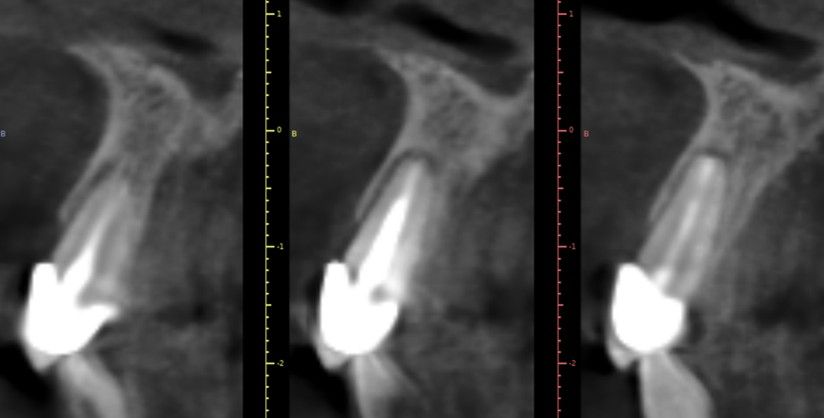

Como valoración preoperatoria, se realizaron registros fotográficos intraorales y extraorales, así como un escaneado intraoral de estudio. Como prueba complementaria, se efectuó un estudio mediante tomografía computarizada de haz cónico (CBCT) (Figura 1), que permitió analizar los factores determinantes para la ejecución de la técnica, tales como el biotipo óseo, la longitud radicular, el hueso residual disponible y la morfología de la cresta alveolar.